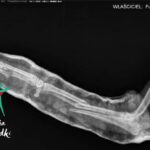

Feel trafił pod naszą opiekę ze złamaniem poprzecznym trzonu kości promieniowej oraz jednoodłamowym złamaniem skośnym trzonu kości łokciowej oraz licznymi ranami na kończynach.

Pomyślnie przeszedł operację, rehabilitację, rany zagoiły się, a FEEL może znów biegać!